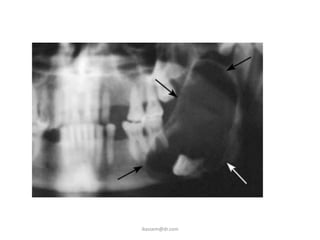

C - the position of the long axis of the impacted tooth in

relation to the long axis of the 2nd molar (winter's

classification):

1-vertical: the long axis of the third molar

is parallel to that of the 2nd molar.

2-horizontal:the long axis of the third

molar is at right angle to that of the

2nd molar .

3-mesioangular impaction.

4-destoangular impaction:

all the previous four classes can come in:

a - lingual deflection.

b - buccal deflection.

5-inverted impaction